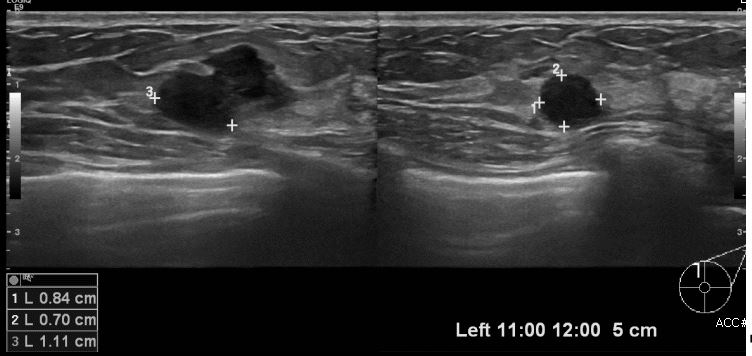

상기환자 좌측 유방에 만져지는 멍울로 내원하신 30대 여성 분으로 좌측 11시에서 12시

방향에서 5cm 떨어진 거리의 멍울 조직검사 시행하여 좌측 침윤성 유관암 진단 되었습니다.